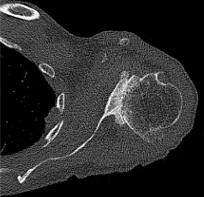

Case one is a 58-year-old male who is an avid golfer with long standing right shoulder pain. Surgical history includes previous Bristow procedure 30 years prior. Current Subjective Shoulder Value (SSV) is 30% and pain is 8/10 at baseline. Active range of motion was 110° of forward flexion, -10° of external rotation and interna rotation to the lateral buttock. Radiographs (Figure 1) and computed topography (CT) scan (Figure 2) show retained implants with loss of joint space, glenoid retroversion, and significant posterior humeral head subluxation. The patient had failed conservative management and was indicated for arthroplasty. Due to significant posterior bone loss and retroversion, an augmented anatomic component was selected for this patient. Radiographs at one year show a well seated glenoid component with restoration of the joint line and a centered humeral head (Figure 3). At five years, SSV had improved to 95% with excellent clinical motion (Figure 4).